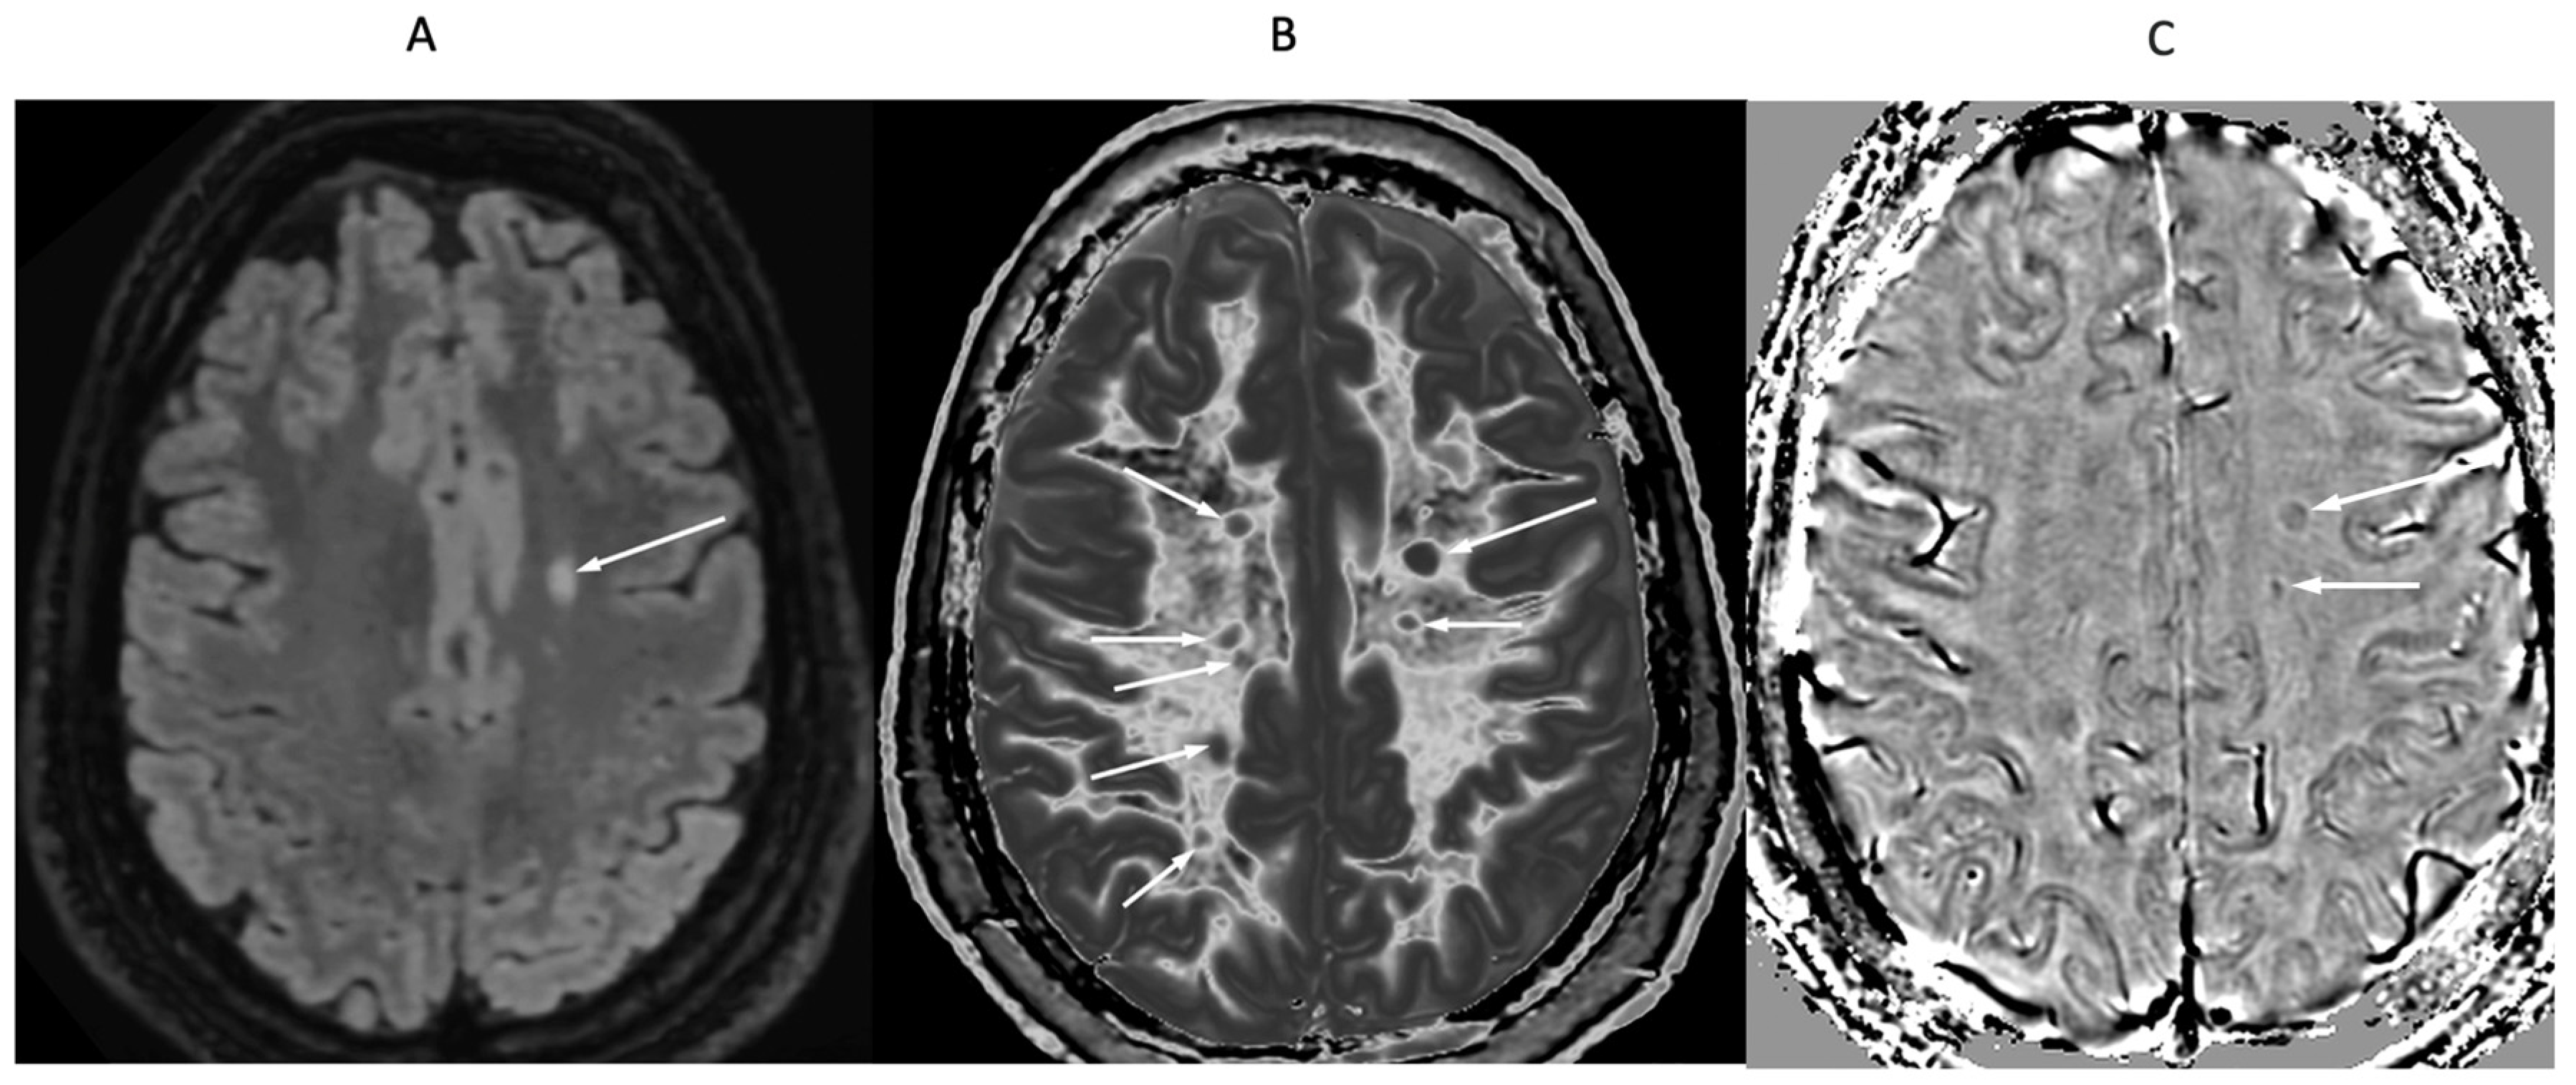

Figure 16.

32-year-old female with MS during a relapse. T

2-FLAIR (A), synthetic narrow mD dSIR (B) and filtered gradient echo (C) images. On the T

2-FLAIR image (A), one lesion is seen (long arrow). The surrounding white matter appears normal. On the dSIR image (B), the lesion shown on the T

2-FLAIR image is seen (long arrow) as well as six other lesions (short arrows). High signal boundaries around lesions are also seen in (B). Some of these lesions show paramagnetic rims on the filtered gradient echo image (arrows) in (C). In addition, most of the white matter in (B) is high signal corresponding to a high grade 4/5 whiteout sign [

1]. The whiteout sign is not seen on the T

2-FLAIR image (A).